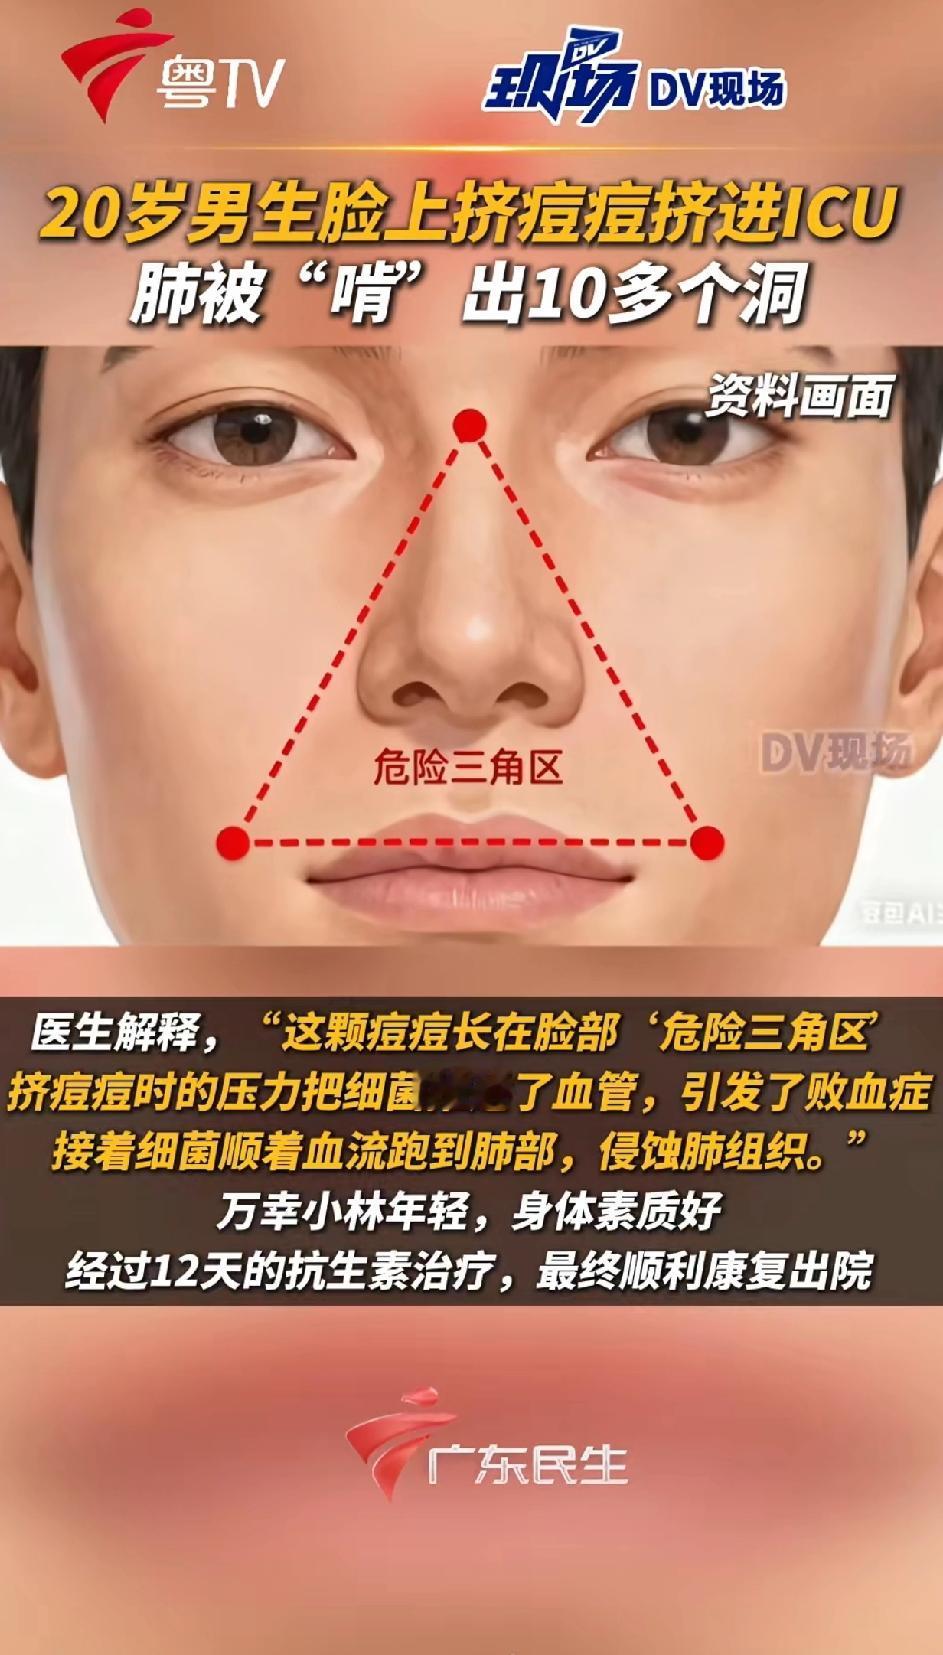

悲剧了!20岁大学生嫌脸上痘痘难看,以为挤掉能快点好,结果,痘痘依旧化脓了,甚至引发高烧,住进了ICU,医生安排CT检查,发现小林肺里有十几个空洞,部分肺组织已经坏死!网友:不知、不知道,一知吓一跳,我都不知道挤了多少个痘痘! 这事儿听着就吓人,谁能想到挤个痘痘能闹到进ICU的地步。小林这情况,医生后来解释说,是因为他挤痘痘的时候,手上的细菌顺着破损的皮肤钻进了血管,一路感染到了肺部,引发了严重的脓毒症。脸上的痘痘看着小,可位置特殊,尤其是鼻子周围那片“危险三角区”,血管直接连着大脑,一旦感染扩散,后果真能要命。 说起来,好多人都有挤痘痘的习惯。对着镜子看到那颗红红的疙瘩,总觉得手痒痒,挤完那一刻还挺有成就感。可很少有人想过,自己的手一天摸这摸那,细菌多着呢,挤的时候稍微没注意,就可能把细菌推进皮肤深层。而且挤痘痘本身就容易把毛囊挤破,让炎症更厉害,本来几天能好的痘,说不定挤完反而肿成大包,留疤都是轻的。 小林这案例算是给所有人提了个醒:脸上的痘痘真不是随便能碰的。尤其是那种又红又肿、摸着还疼的,十有八九是有炎症,这时候挤就是火上浇油。年轻人爱美心切能理解,但比起一时的痛快,还是得讲究方法。长了痘,注意清洁,饮食清淡点,实在严重就去看医生,配点药膏或者口服药,都比自己瞎折腾强。 现在好多人对皮肤问题的认知还停留在“挤挤就好”的层面,觉得医生说的“危险”是小题大做。可真等出事了才明白,身体这台机器精密着呢,一点小伤口处理不好,都可能引发连锁反应。就像小林,本来只是想让脸好看点,结果差点把命搭进去,这教训太深刻了。 各位读者你们怎么看?欢迎在评论区讨论。